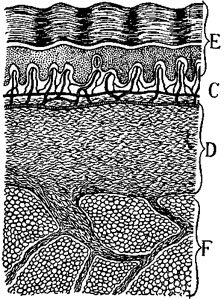

169 The Layers of the Skin

The Lining Surface of the Stomach. Now let us look more carefully at the lining surface of the stomach, for it is very {14}wonderful. Like all other living surfaces, it consists of tiny, living units, or "body bricks" called cells, packed closely side by side like bricks in a pavement. We speak of the mucous membrane, or lining, of our food tube, as if it were one continuous sheet, like a piece of calico or silk; but we must never forget that it is made up of living ranks of millions of tiny cells standing shoulder to shoulder.

These cells are always actively at work picking out the substances they need, and manufacturing out of them the ferments and acids, or alkalies, needed for acting upon the food in their particular part of the tube, whether it be the mouth, the stomach, or the small intestine.

(Greatly magnified)

Showing the mouths of the stomach glands, and the furrows, or folds, of the lining.